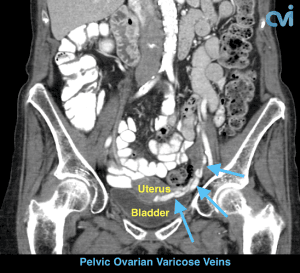

Magnetic resonance imaging (MRI) and computed tomography (CT) is another method to diagnose pelvic congestion syndrome. Our practice requires a CT of the Abdomen and Pelvis with contrast prior to treatment. This allows us to see where the varicose veins are coming from so that we can plan and do the appropriate treatment. Sometimes there are abnormal pelvic veins in addition to the ovarian veins that need treatment. Sometimes PCS can be missed on CT if the contrast injection is not timed appropriately or the vein is not directly measured.

Our specialist who is also a Board Certified Radiologist will review all of your imaging personally to make sure an accurate diagnosis is made. Following an accurate diagnosis, you can then undergo the Ovarian Vein Embolization procedure.